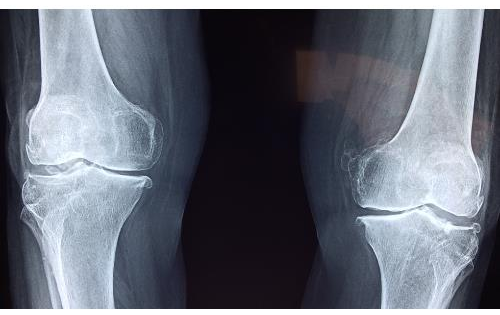

On arrival, her blood pressure was 90/60 mmHg, heart rate of 120 bpm, respiratory rate of 22 breaths per minute, and temperature of 36.5 °C. The patient is pale, diaphoretic, and anxious. The patient is otherwise healthy and has no other significant past medical history. The central nervous system (CNS) examination reveals a Glasgow coma scale (GCS) score of 15, and the patient is alert and oriented. Cardiovascular examination indicates tachycardia with a regular rhythm, weak peripheral pulses, and delayed capillary refill. On auscultation, the patient is tachypneic, but the breath sounds are clear bilaterally. A complete blood count indicates hemoglobin of 10 g/dL, hematocrit of 30%, and other parameters within normal range. Blood coagulation shows prothrombin time (PT), activated partial thromboplastin time (aPTT), and international normalized ratio (INR) within normal range. An X-ray of the affected lower limb reveals no fractures but soft tissue swelling (Figure 1).

Figure 1: X-ray of the Knee Joint showing normal bony alignment and joint space